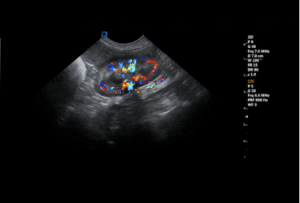

Veterinary ultrasound addresses this challenge directly in daily clinical practice. By allowing clinicians to visualize organs, soft tissues, fluid accumulation, and blood flow in real time, ultrasound often becomes the first imaging modality to guide diagnosis—especially when physical examination and laboratory results are inconclusive.

For this reason, veterinary ultrasound is increasingly used either before or alongside radiography, particularly for soft tissue, abdominal, and cardiovascular evaluations.